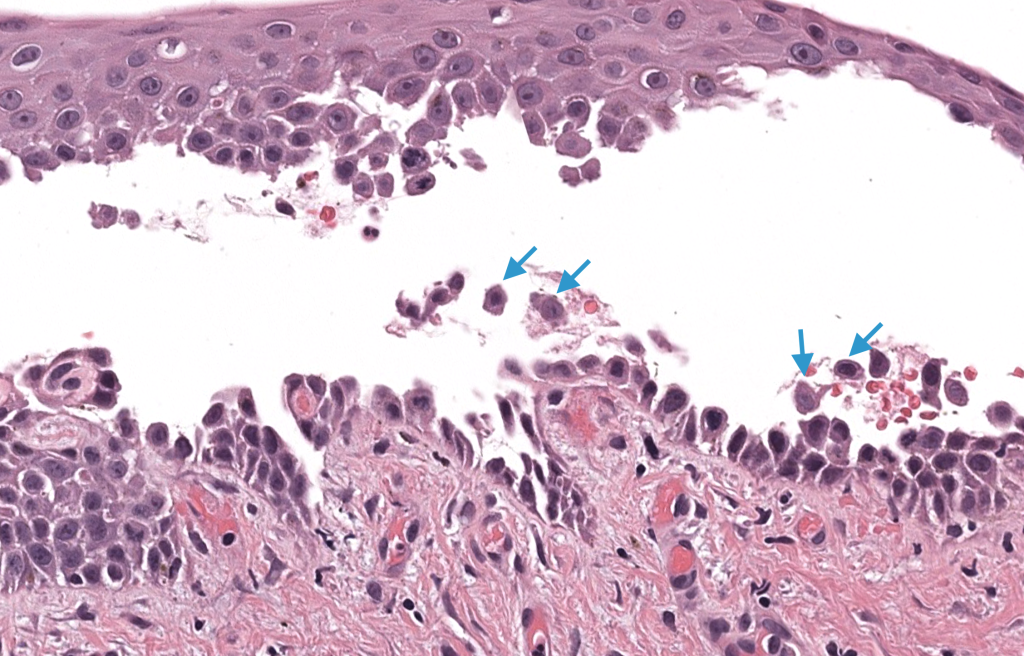

- Histología

- Biopsia de ampolla reciente / borde → ampolla suprabasal + acantólisis + “fila de lápidas”.